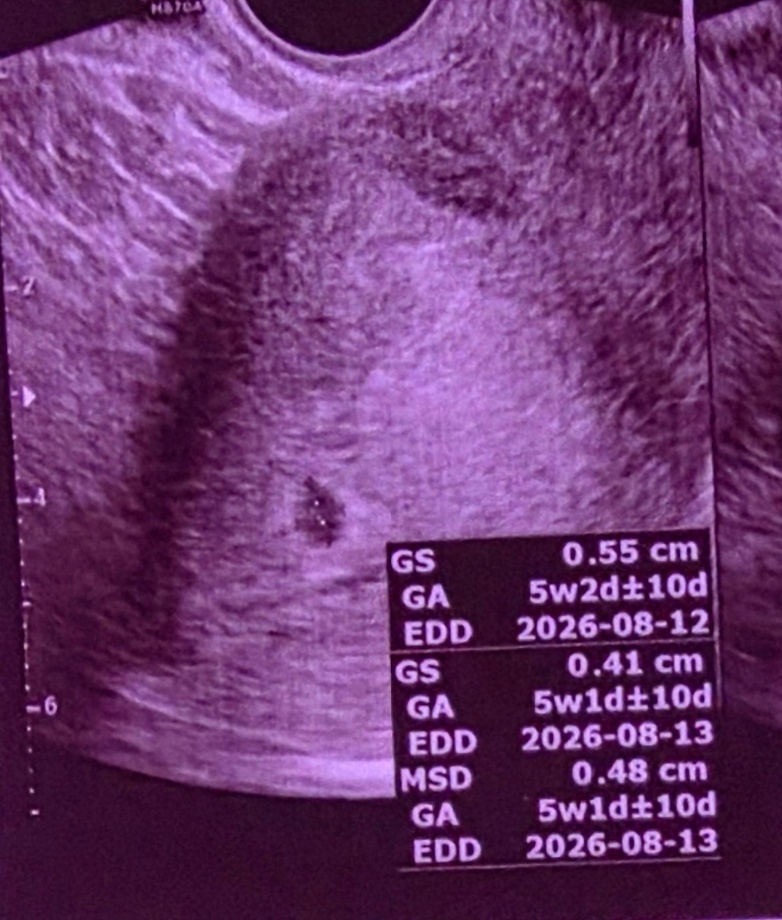

난황은 몇주에 생기는지 지금 초음파에 아기집만 보이는거 같아서용

5주2일차에 보고왔습니다!!